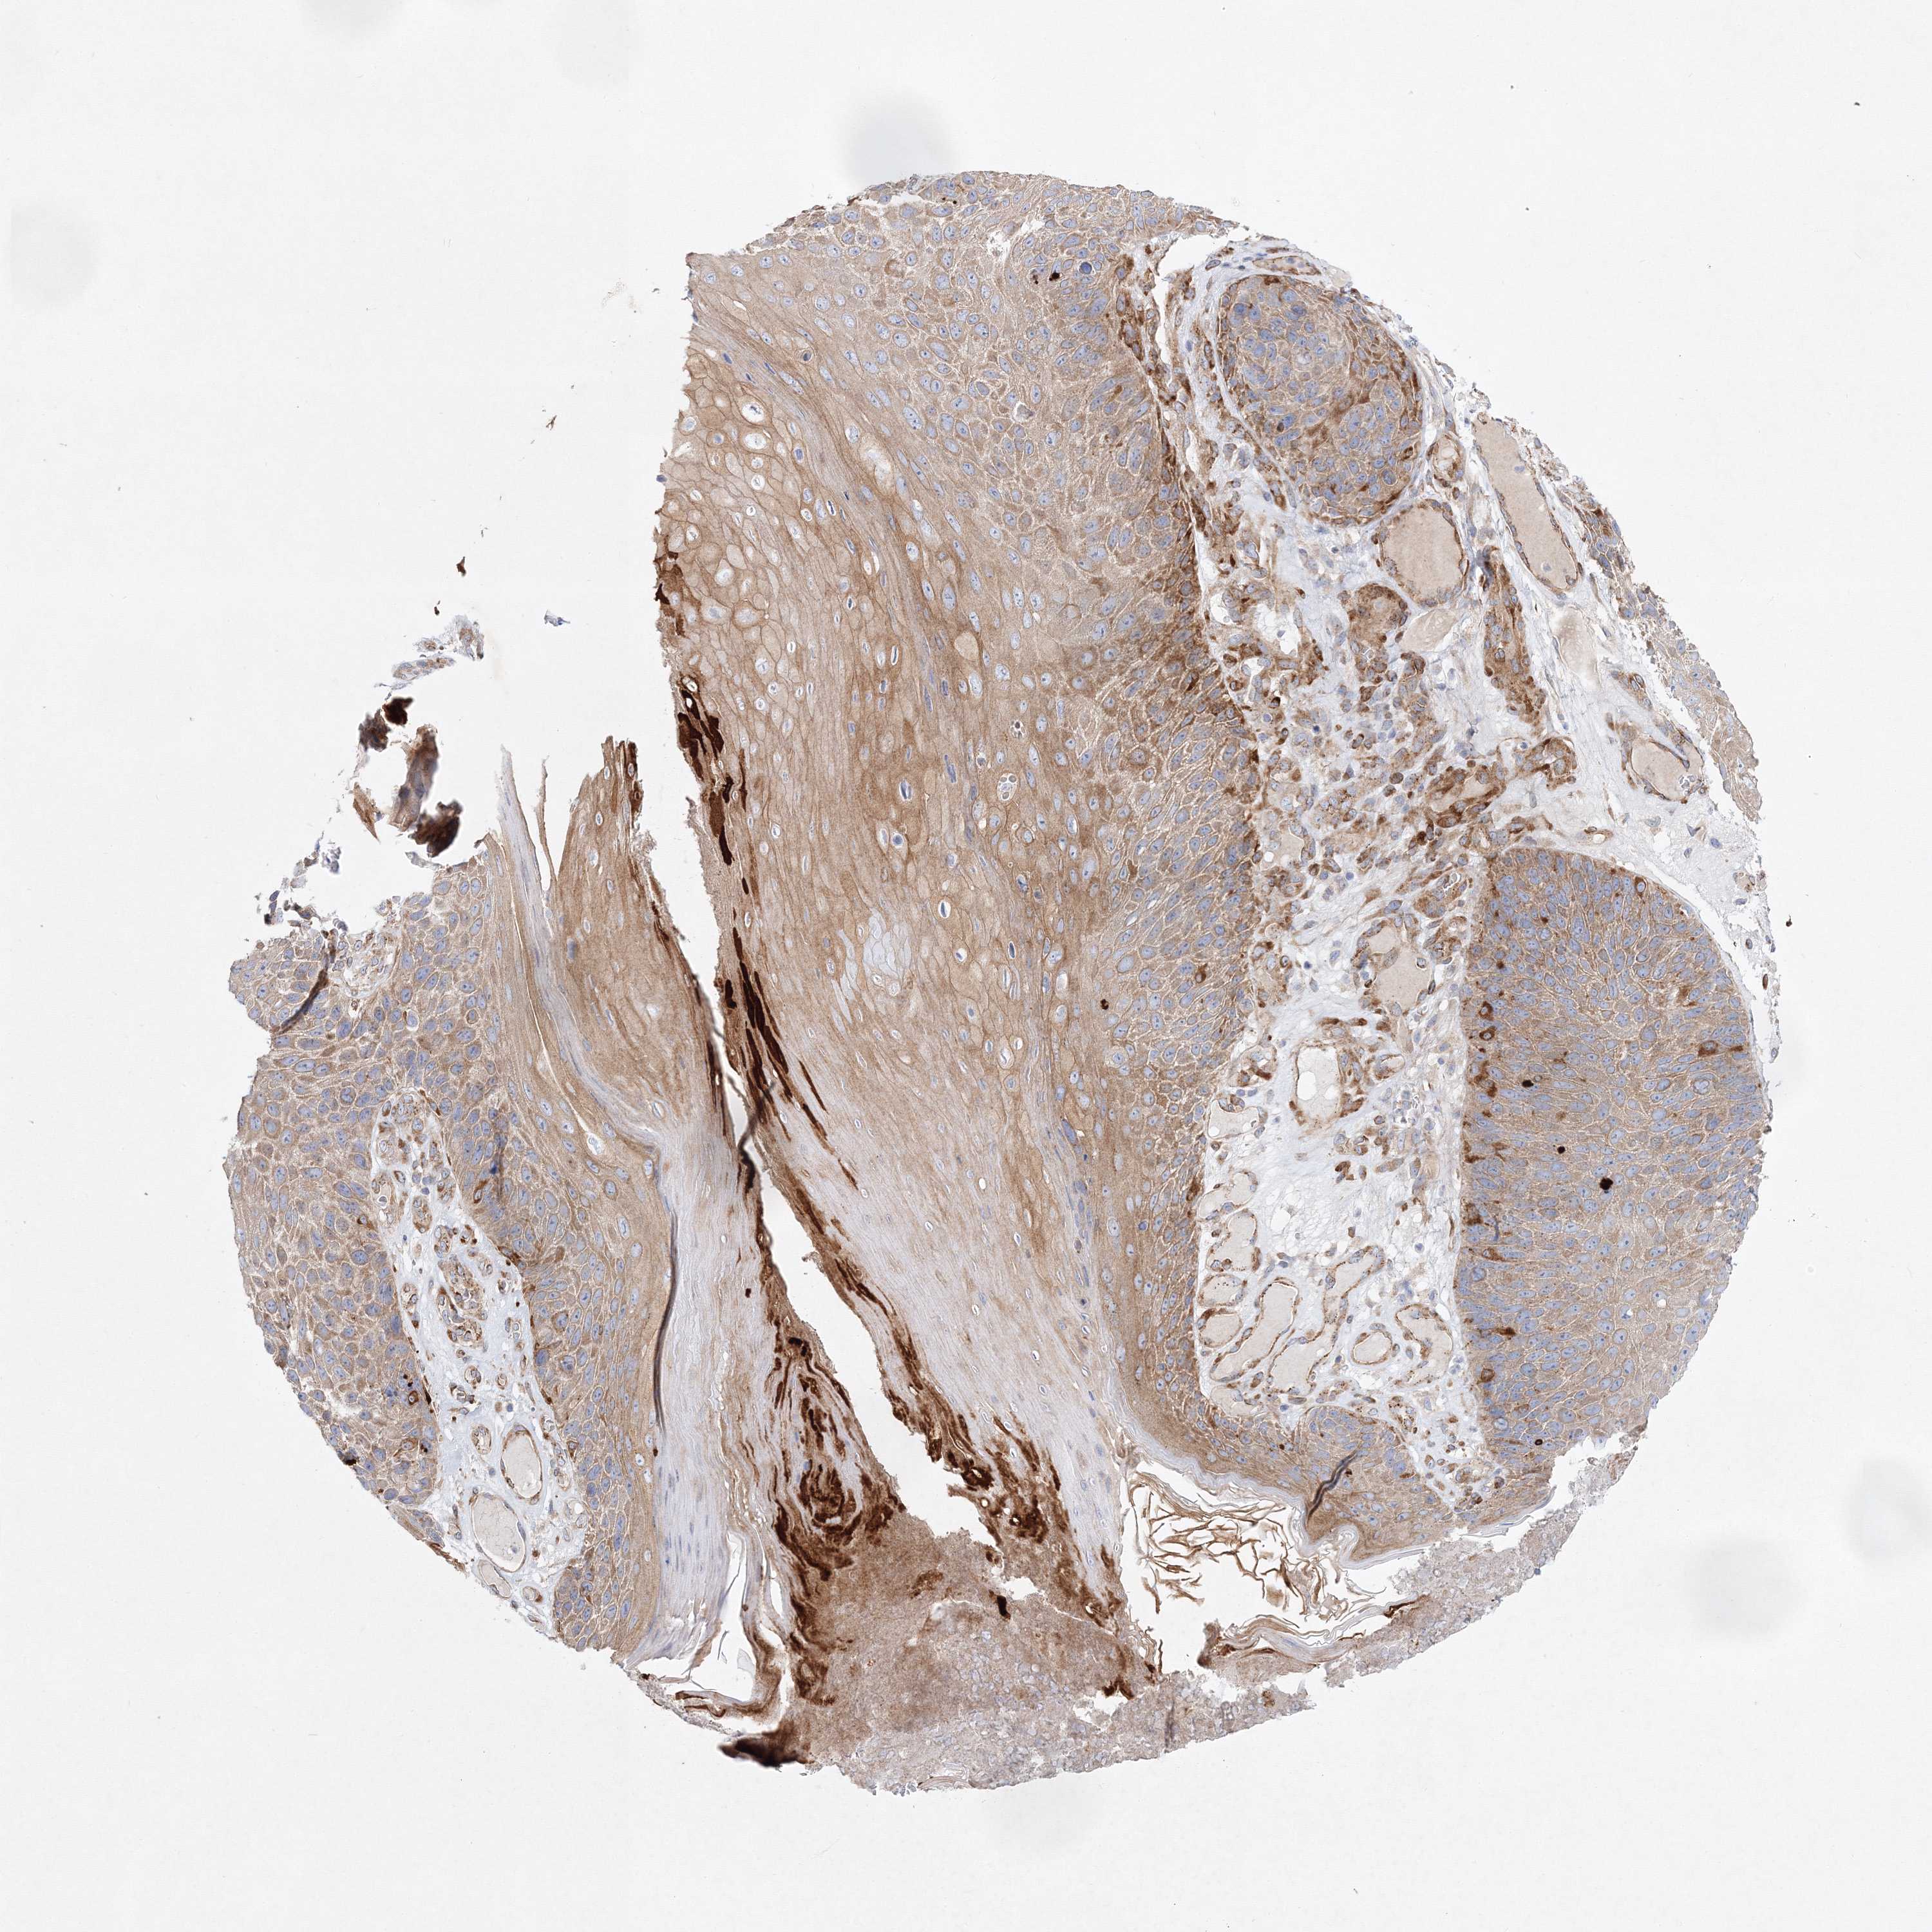

CANCER SKIN CANCER Show tissue menu

Basal cell and squamous cell cancer

SKIN CANCER - Protein expressioni

A mouse-over function shows sample information and annotation data. Click on an image to view it in a full screen mode. Samples can be filtered based on level of antibody staining by selecting one or several of the following categories: high, medium, low and not detected. The assay and annotation is described here.

Each image is clickable and will lead to virtual microscopy that enables deeper exploration of all samples and also displays staining intensity scores, fraction scores and subcellular localization as well as patient and tissue information for each sample.

Antibody HPA035935

Basal cell carcinoma

Squamous cell carcinoma, NOS

Squamous cell carcinoma, metastatic, NOS